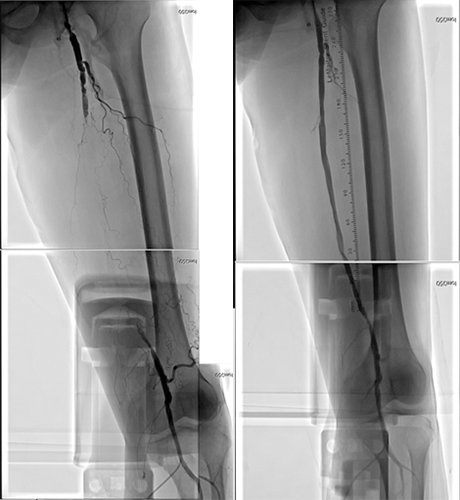

閉塞性動脈硬化症や血液透析患者さんの末梢動脈疾患の難治潰瘍に対して、経皮的血管形成術を施行しております。局所麻酔で行いますので、体力が少ない患者さんや全身麻酔が困難な患者さんにも治療可能です。治療の難易度が高い慢性完全閉塞病変については、必要に応じて両方向性アプローチや特別なテクニックを用いて、治療の成功率を高めるだけでなく、手術時間を短縮するようにしています。また腎血管性高血圧症についても腎動脈形成術による治療も施行しています。